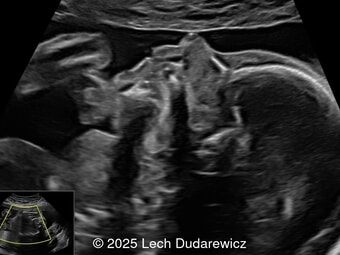

A 26-year-old primigravida with no significant past medical or family history was admitted at 18 weeks of gestation with preterm premature rupture of membranes. At 20 weeks of gestation, a detailed fetal ultrasound was performed under conditions of severe oligohydramnios, followed by fetal magnetic resonance imaging (MRI). Non-invasive prenatal testing (NIPT) for common aneuploidies was negative.